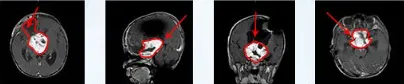

珍女士一家在孩子的治疗路上经历了不少波折。5岁的儿子因突发视力下降就诊,影像显示鞍区巨大占位,累及额叶和第三脑室。初次看到磁共振时,珍女士难以置信:"肿瘤几乎占了大脑三分之一,症状却只是视力下降?"

随后珍女士带孩子赴德求医。意外情况出现:此前诊断为额叶胶质瘤,在德国被确诊为视神经胶质瘤。诊断变更使原方案推翻,在巴特朗菲教授与Di Rocco教授协作下,新方案逐渐成型。

最终手术取得极大成功。肿瘤完全切除,病理为低级别毛细胞型星形细胞瘤。待一过性发热和尿崩好转后,珍女士得知孩子视力改善,术后14天便带着已能行走的儿子回国。随访未见复发,视力逐步恢复,已能准确抓取物品,手术成功保住了视功能。